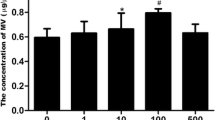

To investigate the effects of in vitro uremic conditions, cultured KMSCs were treated with IS and p-cresol, which inhibited cell proliferation over the course of 24 h relative to vehicle control (Fig. 1a). Additionally, we observed that cell viability following exposure to various IS concentrations (0.25, 1.0, and 2.5 mM) decreased in a dose-dependent manner (by 6.5 %, 11.7 %, and 23.1 %, respectively) as compared with vehicle control (P = 0.054, P = 0.001, and P < 0.001, respectively). In addition, p-cresol treatment decreased the cell viability in a dose-dependent manner (0.05 mM by 3.3 %, 0.1 mM by 8.8 %, and 0.25 mM 21.7 %, and 0.5 mM by 37.6 %) as compared with vehicle control (P = 0.234, P = 0.007, P < 0.001, and P < 0.001, respectively) (Fig. 1b). RT-PCR analysis revealed significant decreases in mouse EPO mRNA levels following IS and p-cresol treatment relative to vehicle control (mouse EPO/β-actin: IS, 0.57 ± 0.05 vs. 1.22 ± 0.08, P = 0.002; p-cresol, 0.58 ± 0.14 vs. 1.00 ± 0.13, P = 0.004) (Fig. 1c).

Viability and erythropoietin (EPO) mRNA levels in kidney-derived mesenchymal stem cells (KMSCs) under uremic conditions. a Cell proliferation of KMSCs treated with either vehicle control or indoxyl sulfate (IS) according to microscopy analysis. b Relative cell viability of KMSCs according to IS and p-cresol concentrations. c EPO mRNA levels in vehicle control cells relative to those treated with IS or p-cresol, respectively. Results represent the mean ± standard error of the mean of three independent experiments. *P < 0.05 vs. vehicle control, Krukal–Wallis test